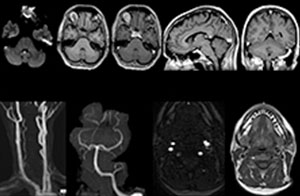

To minimize the time taken to perform scans, rapid MRI examination protocols (ExamCards) were developed, shortening the total scanning time to even less than 10 minutes in some exams. Techniques like mDIXON (modified DIXON) are used for robust capturing of fat-free MRI images in a hectic ED environment.

“We use mDIXON TSE extensively in our spine imaging in the emergency room,” says Dr. Karis. “It’s particularly nice in that it is very robust with regard to susceptibility type of problems that would come up with traditional spectral fat-saturated images; these problems are essentially eliminated with the mDIXON technique. In our ED environment it’s really nice to have the fat-free imaging that goes along with the mDIXON technique.

“For the thoracic and cervical spine routine non-contrast exam, for example, we perform one mDIXON T2 TSE sequence, which provides us with two outputs: the fat-and-water-together T2-weighted images, as well as the water-only sagittal T2-weighted images. And then we also perform an axial gradient echo exam.”

A range of protocol sheets was developed to help ensure that referring physicians order the most appropriate MRI exam. The optimized MRI protocols also include 3D contrast-enhanced imaging, allowing neurosurgeons to comfortably use the isotropic data in the operating room while performing stereotaxic surgery.